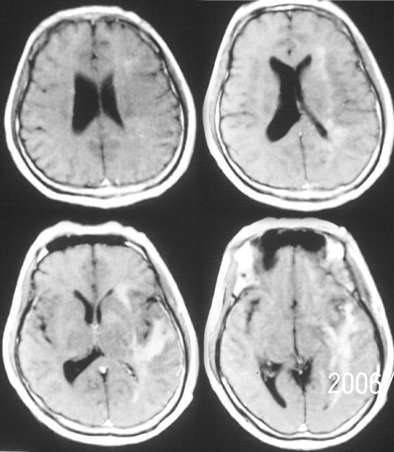

mr是增强

左侧基底节额颞叶稍长t1长t2信号,增强见边缘与脑回样强化,作侧脑室变窄。ct平扫呈等与扫地密度以等密度为主。考虑1脑炎。2脑肿瘤[淋巴瘤]

ct示左颞叶等,略低密度影,mr示左额颞叶t1wi呈低信号,t2wi呈高信号,增强后边缘不均匀强化,左侧脑体部明显受压,考虑脑梗塞可能性大

首先考虑脑梗塞,肿瘤mri表现多为长t2信号,增强后多有明显的不均匀强化,本病例占位征象明显,如果是肿瘤恶性度是偏高的,增强后应该有明显的强化表现。临床病史比较短暂,增强后强化呈条片状,梗塞在三天为水肿高峰,占位明显。综合考虑脑梗塞可能性大。